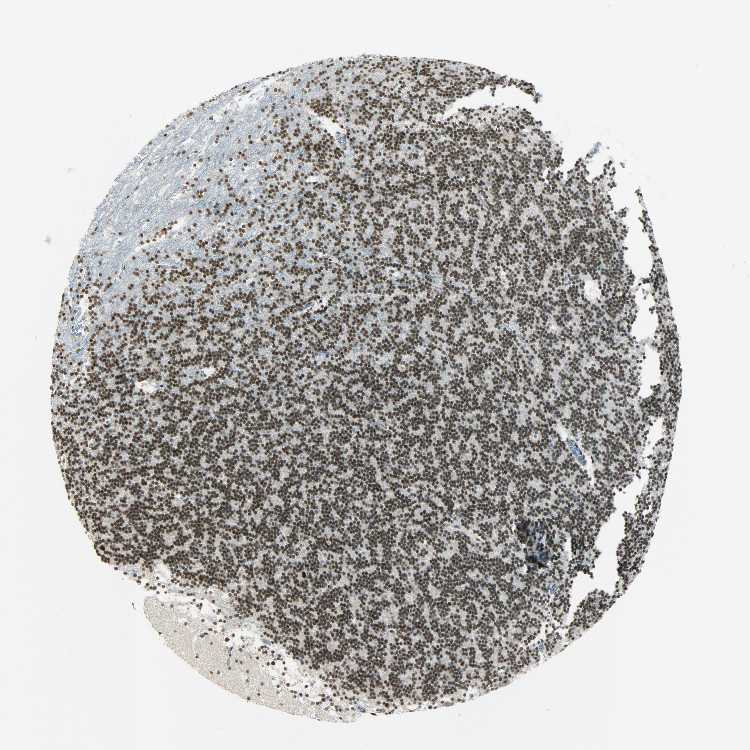

CEREBELLUM - Antibody stainingi

Antibody staining in the annotated cell types in the current human tissue is reported as not detected, low, medium, or high, based on conventional immunohistochemistry profiling in selected tissues. This score is based on the combination of the staining intensity and fraction of stained cells.

Each image is clickable and will lead to virtual microscopy that enables deeper exploration of all samples and also displays staining intensity scores, fraction scores and subcellular localization as well as patient and tissue information for each sample.

Antibody HPA004890

Purkinje cells High

Cells in granular layer High

Cells in molecular layer High